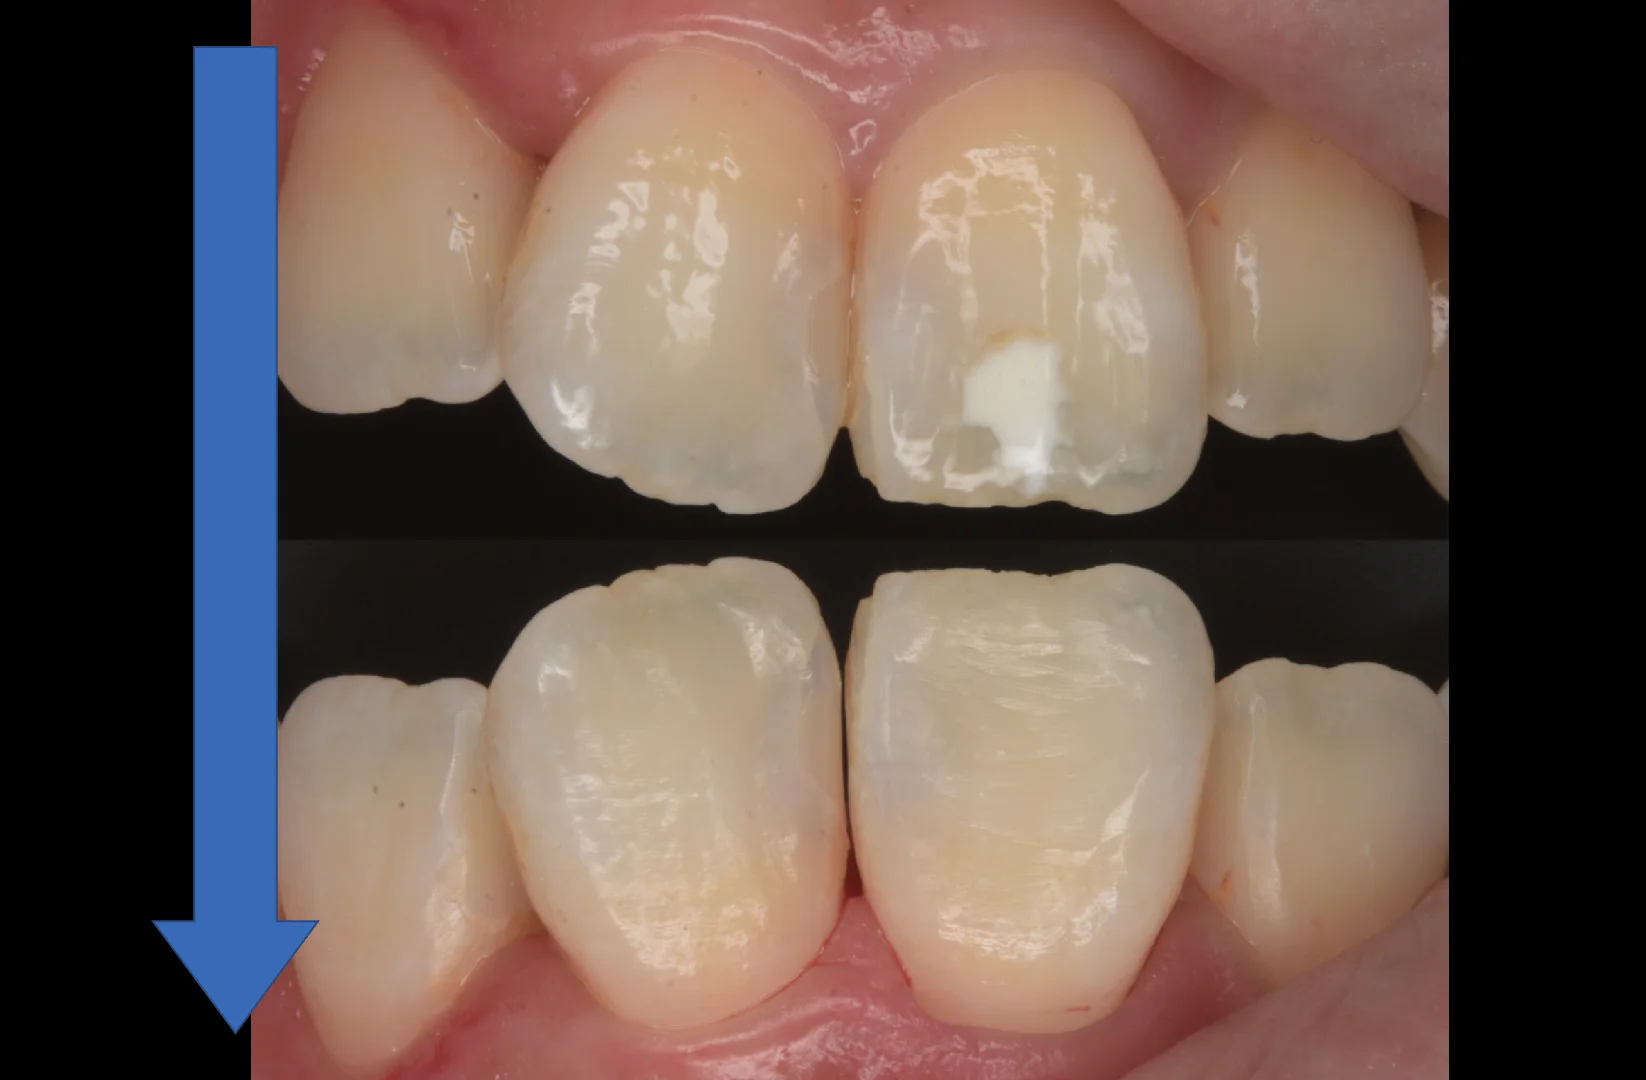

さて。ではこのあとどのようにリカバリーをしたのかというと・・・

こんな感じで残存した部分だけ削って詰めた感じです。

他の歯がそうでしたので、歯ブラシなどでの削れた表面性状をやや強めに表現しています。

随分と目立たなく、違和感がなくなったのが分かるかと思います。